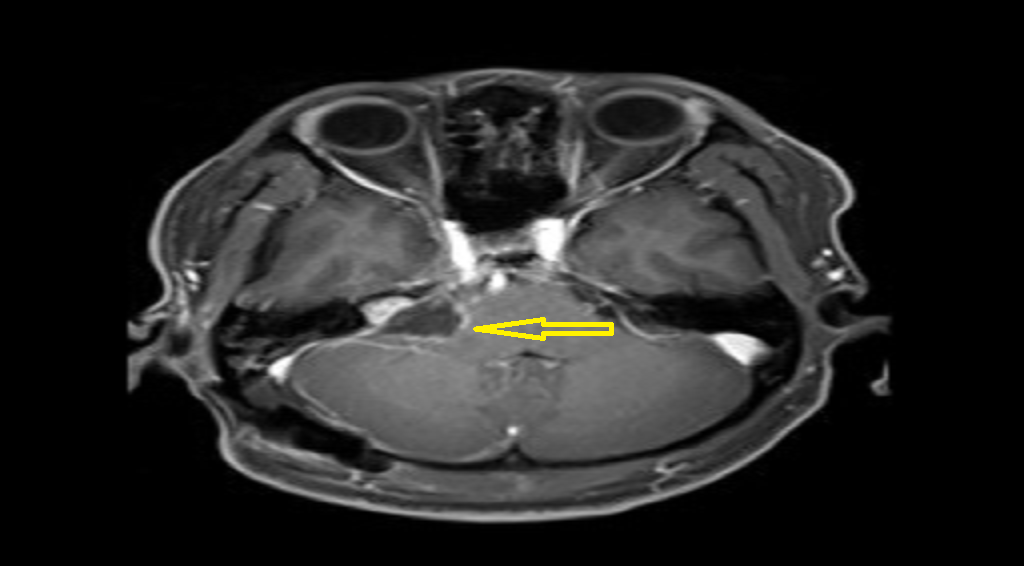

■ 王先生的肿瘤位于右侧桥小脑角区考虑为听神经瘤可能性大,虽然较王女士的肿瘤小,但该肿瘤已严重侵犯王先生内听道,还有瘤内出血现象,必须马上手术。术中手术医师全神贯注在电生理监测下细致地避开重要血管,将肿瘤组织与面听神经、三叉神经分离,成功将肿瘤完整切除。

(术前)

(术后)